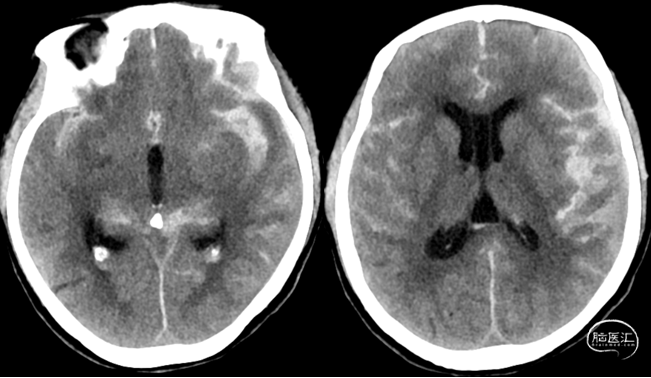

头颅CT

术前

术后第一天